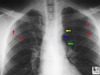

coarctation of aorta dx

-post ductal MC -initial test- BP -doppler echo- confirmatory -imaging: -scalloping of inferior border of ribs due to enlargement of intercostal arteries for collateral supply -"3" sign -red arrows point to rib notching caused by the dilated intercostal arteries -yellow arrow points to the aortic knob -blue arrow to the actual coarctation -green arrow to the post-stenotic dilation of the descending aorta